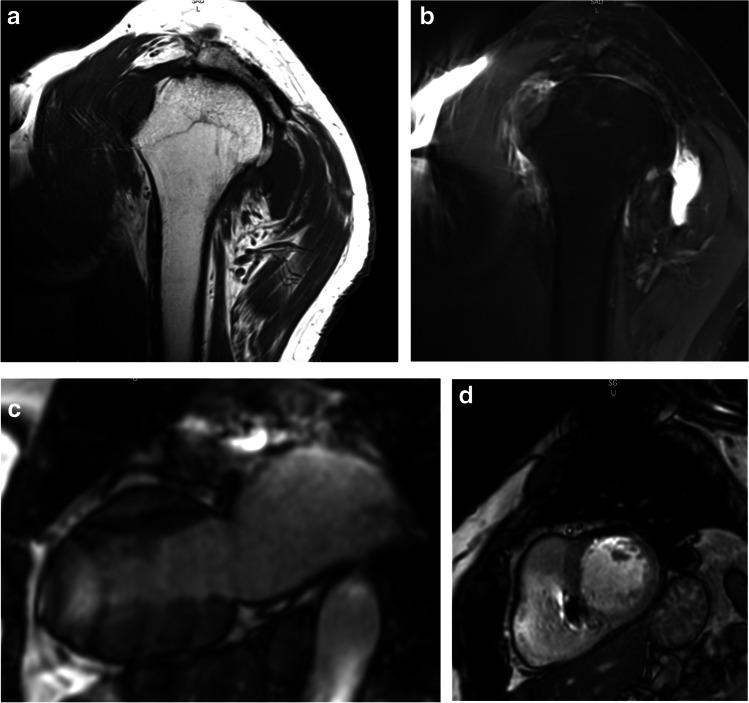

A total of 267 implanted patients underwent MRI examination (brain, cardiac, shoulder, cervical spine) at 1.5 (n = 126) or 3 T (n = 141). MRI-related device complications, lead electrical performances stability at 1-month post-MRI, proper functioning of the automated MRI mode and image quality were evaluated.

Freedom from MRI-related complications at 1 month post-MRI was 100% in both 1.5 and 3 T arms (both p < 0.0001). The stability of pacing capture threshold was respectively at 1.5 and 3 T (atrial:: 98.9% (p = 0.001) and 100% (p < 0.0001); ventricular: both 100% (p < 0001)). The stability of sensing was respectively at 1.5 and 3 T (atrial: 100% (p = 0.0001) and 96.9% (p = 0.01); ventricular: 100% (p < 0.0001) and 99.1% (p = 0.0001)). All devices switched automatically to the programmed asynchronous mode in the MRI environment and to initially programmed mode after the MRI exam. While all MR examinations were assessed as interpretable, artifacts deteriorated a subset of examinations including mostly cardiac and shoulder ones.

在 1.5 和 3 T 臂中,MRI 后 1 个月时无 MRI 相关并发症的比例均为 100%(均 p<0.0001)。起搏捕获阈值的稳定性分别为 1.5 和 3 T(心房:98.9%(p=0.001)和 100%(p<0.0001);心室:均为 100%(p<0.0001))。感知的稳定性分别为 1.5 和 3 T(心房:100%(p=0.0001)和 96.9%(p=0.01);心室:100%(p<0.0001)和 99.1%(p=0.0001))。所有设备在 MRI 环境中自动切换至程控的异步模式,并在 MRI 检查后切换至初始程控模式。尽管所有 MR 检查均被评估为可解读,但在部分检查中出现了伪影,主要是心脏和肩部检查。